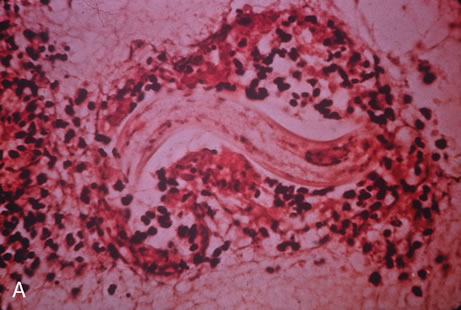

Any cell type may be infected, appearing larger than normal (cytomegalic) and demonstrating eosinophilic intranuclear “owl's eye” and smaller intracytoplasmic viral inclusion bodies, which are better seen with Giemsa or Papanicolaou's stains (Fig. 8). Histologic examination of tissue specimens, including bronchoalveolar lavage fluid and urine, may be useful for diagnosis.